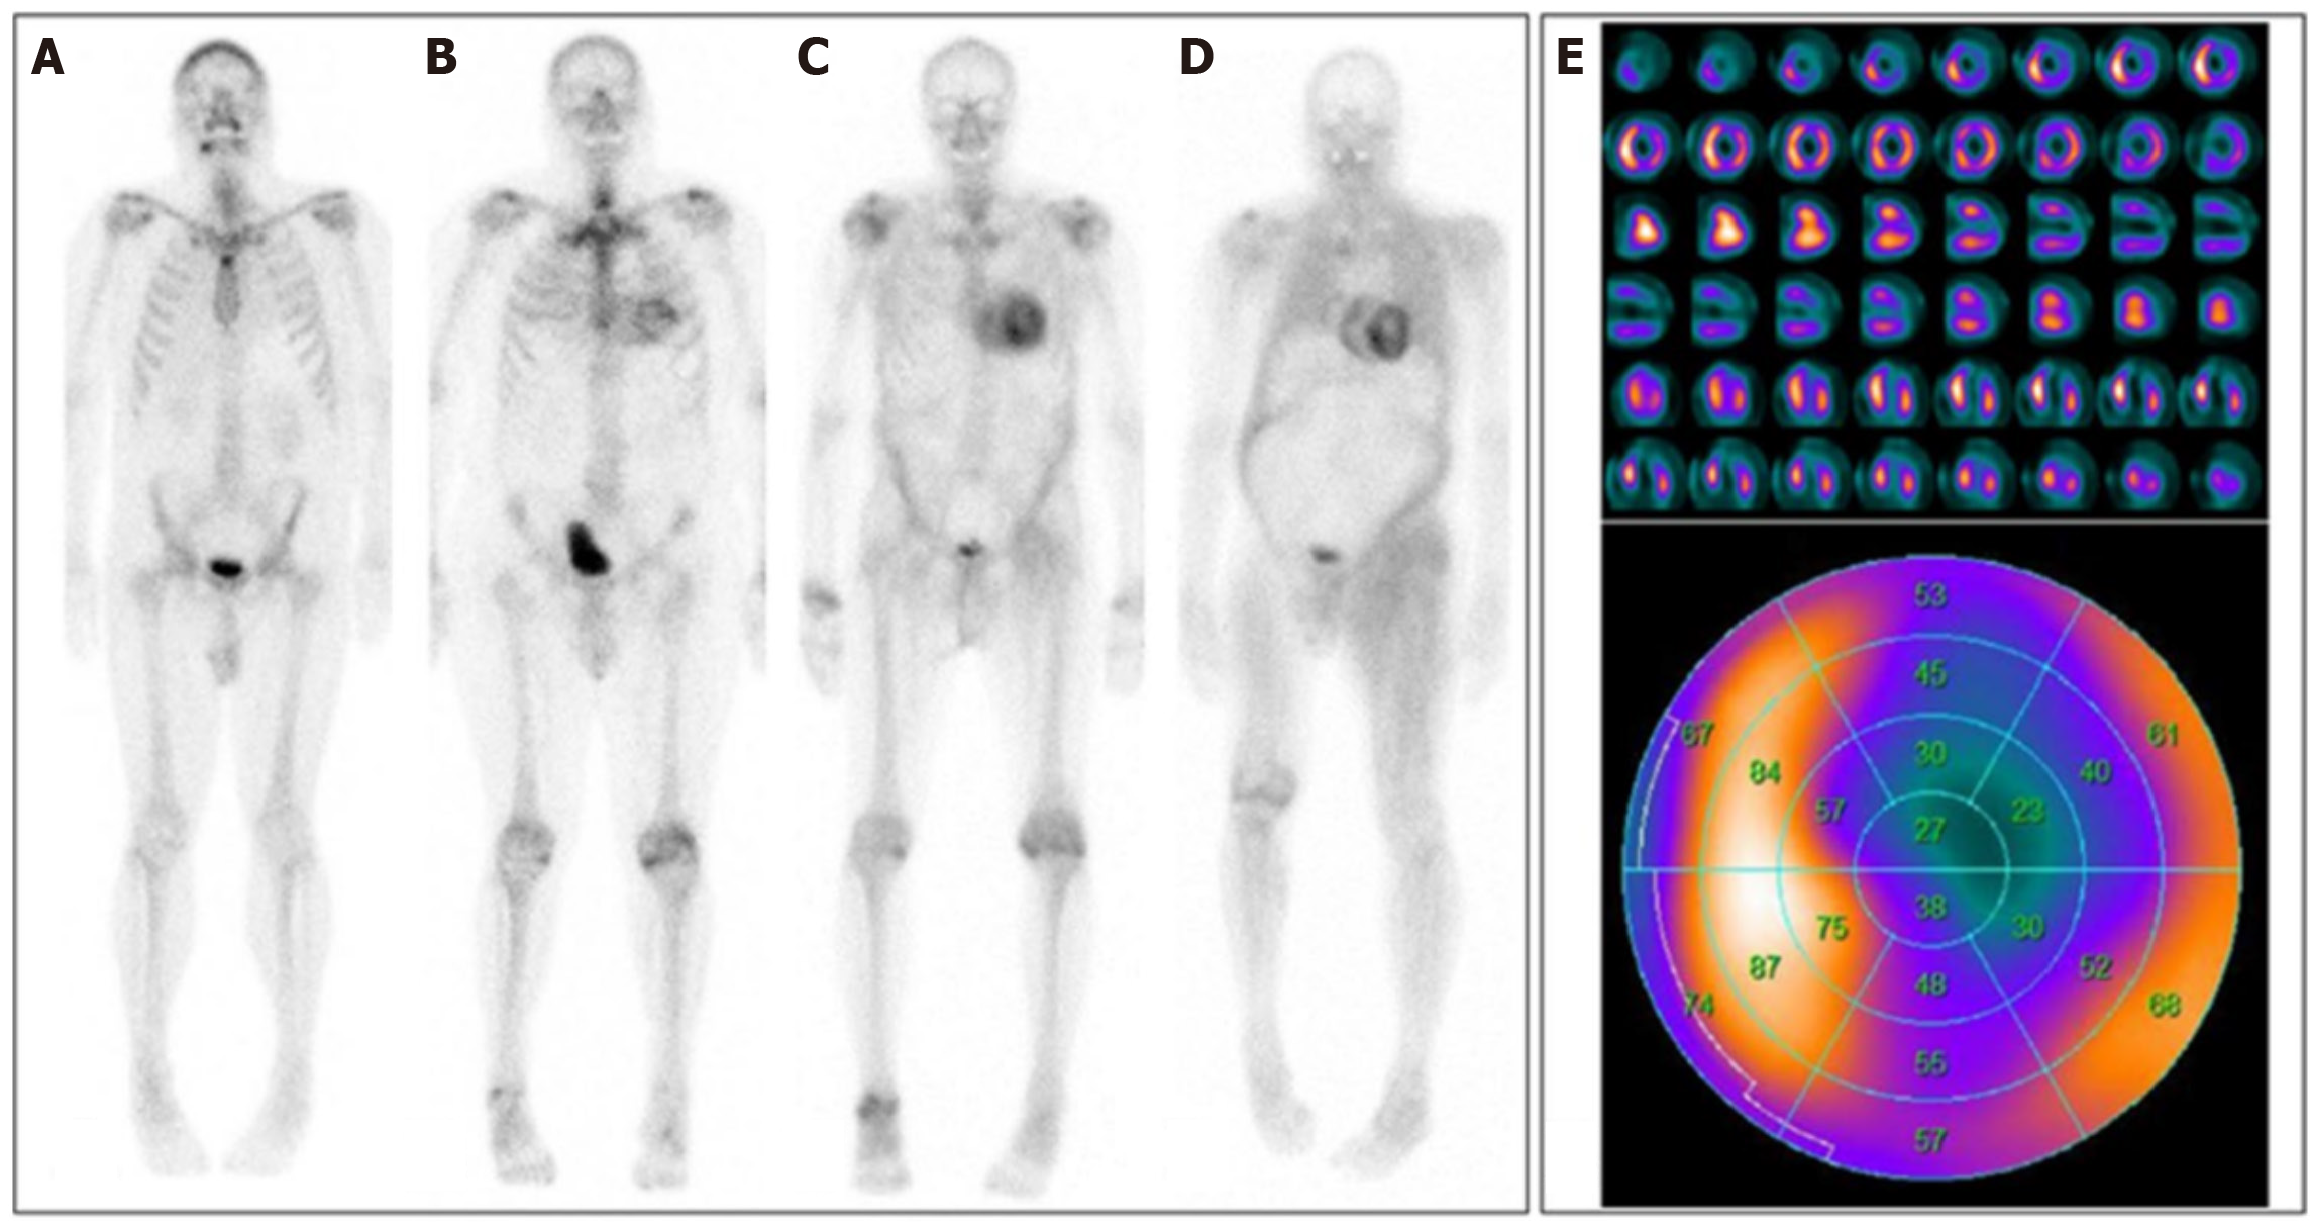

Figure 3 Planar 99mTc-DPD scintigraphies of four different patients.

A: No cardiac uptake (Perugini score 0); B: Light cardiac uptake with preserved delineation of bone tissue (Perugini score 1); C: Strong cardiac uptake above that of bone tissue and increased soft-tissue uptake, particularly in the shoulder, abdominal wall, and gluteal region (Perugini score 2); D: Strong cardiac and soft-tissue uptake with no discernable bone-tissue uptake, suggesting difuse amyloid soft-tissue infltration (Perugini score 3); E: Single-photon emission computed tomography imaging: Short axis, vertical long axis, and horizontal long axis slices at the top and the corresponding polar plot at the bottom; white/yellow indicates high uptake; blue/black indicates little or no uptake[38]. Citation: Yilmaz A, Bauersachs J, Bengel F, Büchel R, Kindermann I, Klingel K, Knebel F, Meder B, Morbach C, Nagel E, Schulze-Bahr E, Aus dem Siepen F, Frey N. Diagnosis and treatment of cardiac amyloidosis: Position statement of the German Cardiac Society (DGK). Clin Res Cardiol 2021; 110: 479-506. Copyright© The Authors 2021. Published by Springer Nature. The article is open access (Supplementary material).